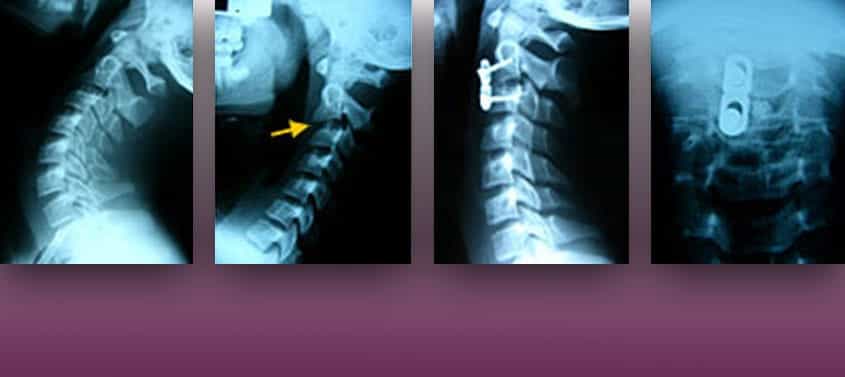

Luxacions Vertebrals

Última actualització: 20/03/2026, Dr. Miguel B. Royo Salvador, Número de col·legiat 10389. Neurocirurgià i Neuròleg. Definició Es defineix com a luxació la sortida d’un os del seu lloc. En el cas de la columna vertebral, la luxació vertebral suposa la pèrdua d’alineació de la mateixa i implica el trencament de lligaments i fractures vertebrals, […]